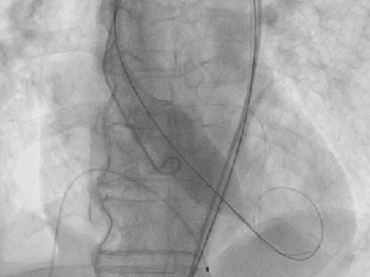

最终影像

术后复盘:因症为制,发挥显著优势